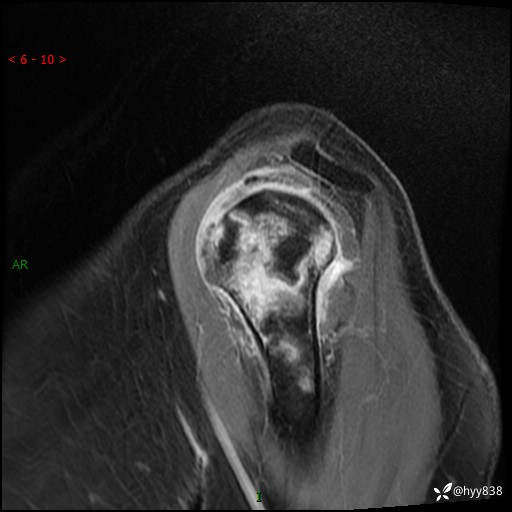

肱骨正侧位片

肱骨MRI平扫(axi T1WI+cor T2WI-fs)+CE-fs(COR+SAG)